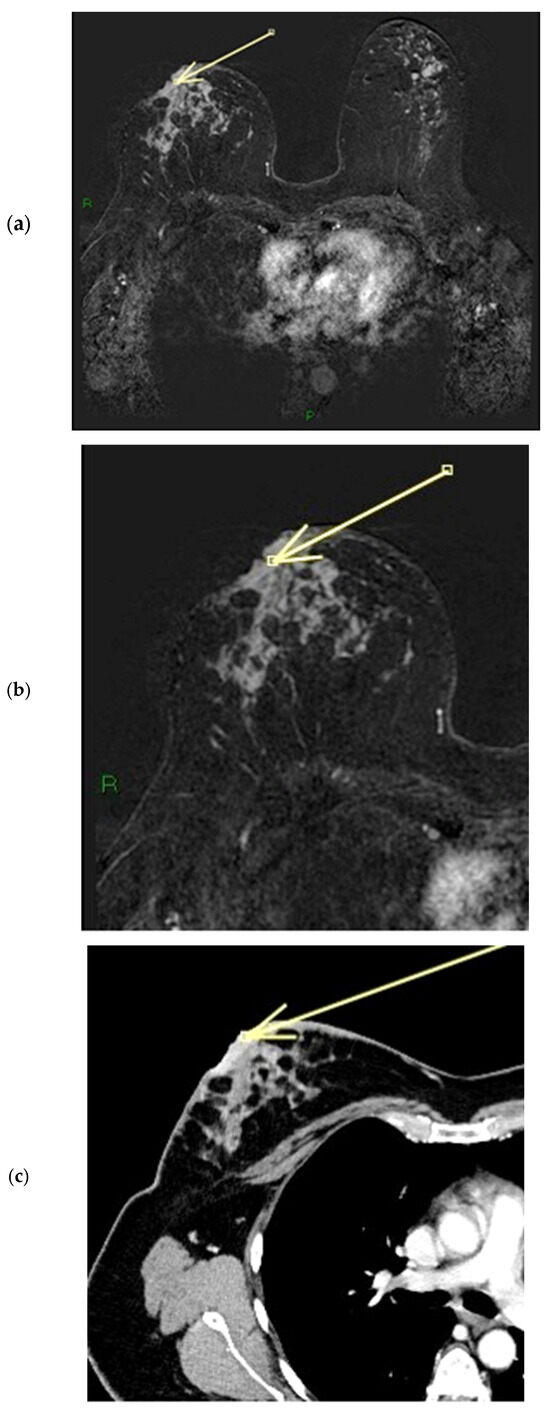

Figure 7.

(a–c) Patient’s name M.E. In the post-contrast fat-suppressed T1 sequences and in the MIP (maximum intensity projection) reconstruction of the first post-contrast fat-suppressed T1 sequence, we notice a gross area of pathological enhancement which affects the external quadrants of the left breast and infiltrates the nipple, without retraction (a,b). During ce-MR, SLE and NEZ enhancement patterns are present; the arrow indicates mild linear INE of the left breast nipple (c).

Figure 8.

(a,b) Patient’s name M.E. The ce-CT scan shows enhancement of the base of the left nipple alone (no body; arrow). Morphology of the nipple is everted.